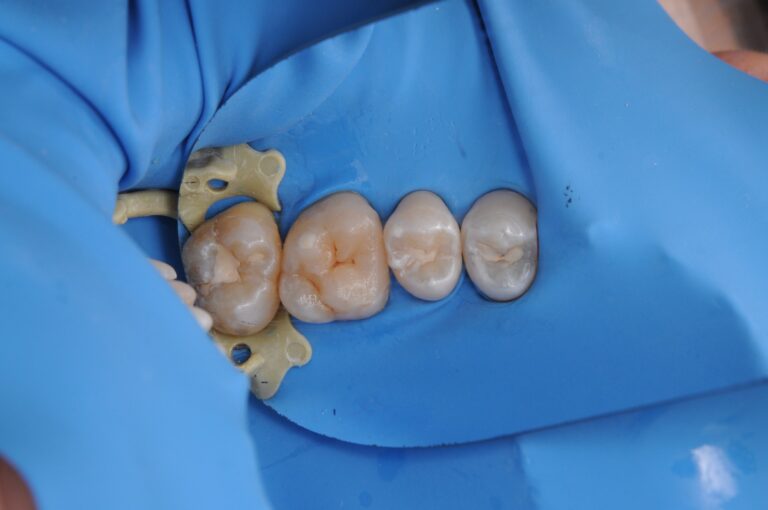

Third image: isolation and cleanliness are the key to a successful result.

We isolated the tooth using a rubber dam

and worked under максимально sterile conditions.

Precision, a dry working field, full visibility of every detail —

all of this is essential to:

• remove all decay

• preserve healthy tooth structure

• achieve perfect adaptation of the filling

Final result: the filling is indistinguishable from the natural tooth.

It replicates the shape, color, and shine of the original tooth.